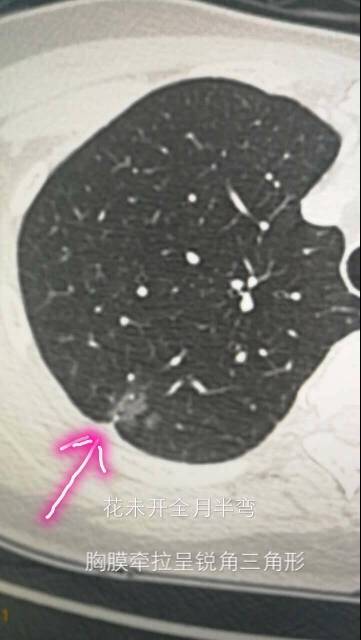

先看第一位患者,简称月半弯。她因为发现肺里面有磨玻璃影,咨询陈医生。磨玻璃影如图所示。

她们两位提供的病灶,都可以称为磨玻璃影,就像玻璃上被砂纸磨过,留下很粗糙的一片。

同时邻近胸膜的地方,都有点牵拉,就是胸膜局部有牵拉出一点。

大家仔细看一下两位的胸膜牵拉,月半弯的比较锐利,拉扯出来的部位呈三角形。而希望的片子里,拉扯出来的部位没那么锐利,绝呈一点不规则的方形。

而希望觅友的胸膜牵拉呢,则比较接近方形,最重要的是,没有症状,体检发现的。所以陈医生最初建议她定期复查。

但是,随着了解的深入,陈医生翻脸了,让她抓紧去手术。为什么呢?大家看看讨论截图就明白了。